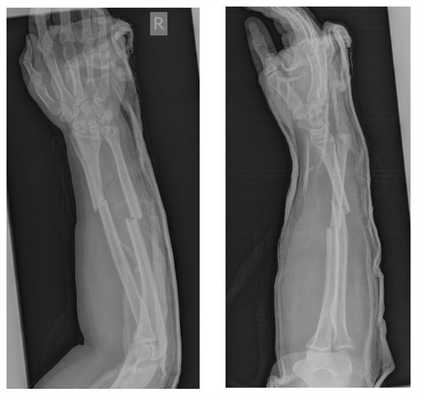

Ниже представлен клинический пример лечения пациента с переломом предплечья.

Пациент Х. Травма в быту, упал на бордюрный камень, получил закрытый перелом обеих костей правого предплечья со смещением, разрывом дистального радио-ульнарного сочленения. Обратился в РТП, выполнены рентгенограммы. Наложена гипсовая лонгетная повязка.

Пациент обратился в К+31, учитывая характер перелома пациенту предложено оперативное вмешательство.

Выполнен остеосинтез обеих костей правого предплечья метафизарными пластинами 3,5 мм, фиксация дистального радио-ульнарного сочленения винтом.

Внешний вид конечности после операции, угловая деформация устранена. Сегмент конечности стабилен, движения в локтевом и лучезапястном суставах не ограничены, ротация предплечья ограничена из-за наличия позиционного винта, который будет удаляться через 6 недель.

Реннтгенограммы после операции.

Такой остеосинтез весьма стабилен и позволяет начать реабилитацию уже через сутки после операции. Форсированные нагрузки на предплечье естественно ограничены до рентгенологического подтверждения консолидации. Рентгенконтроль целесообразно производить через 6 и 12 недель. При хорошо выраженных признаках сращения полная нагрузка возможна через 12 недель после операции.